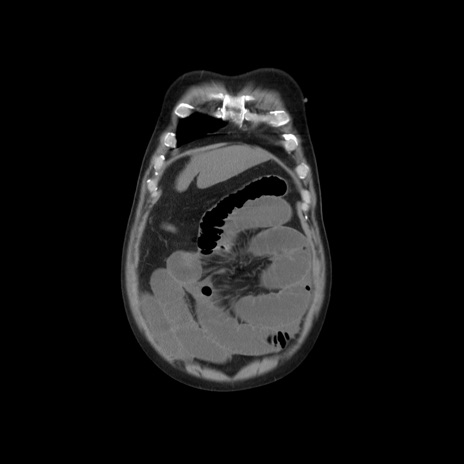

横断像

【症例】 60歳代男性

【主訴】 腹部膨満、嘔吐

【現病歴】5日前頃より倦怠感を認め食事量減少し4日前の朝嘔吐、食事摂取困難となった。 3日前近医受診し点滴施行され整腸剤などを処方された。 当日他院を受診し、腹部膨満著明、炎症反応の上昇(CRP10.8、WBC11200)あり、紹介受診となる。

【身体所見】 意識JCS1 受け答えがはっきりしないBP 111/57mHg、 P 67bpm、、BT35.2°C、SpO2 97%(RA)、 腹部:膨隆、打診で鼓音あり、全体的に圧痛有り、腸蠕動音(-)、反跳痛ははっきりせず。

【データ】WBC 11400、CRP 14.20